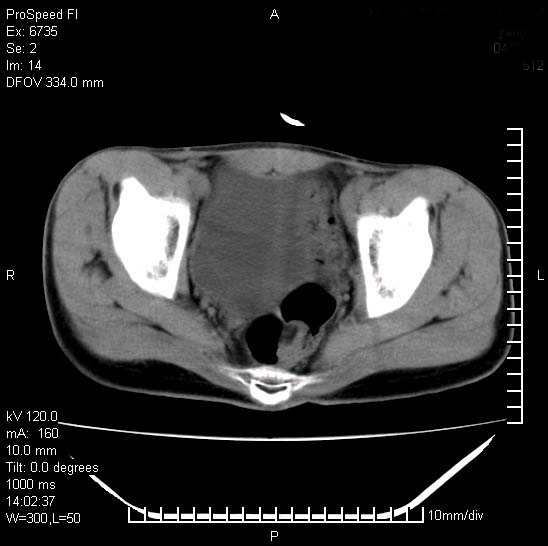

患者自诉胯部疼痛两年余,在当地服用中药,半月前至本院考虑骶髂关节结核,给予抗痨治疗。现发展至右下肢疼痛明显,活动受限,以膝关节处明显,拍膝关节平片无明显异常。

两侧骶骼关节改变,考虑强直性脊炎

左侧骶髂关节面限局性骨破坏,边缘硬化关节腔见钙化物;不出外tb

右侧骶髂关节也有类似改变,只是较左侧轻,首先考虑强直性脊柱炎,不除外结核,建议作hla-b27检查。

典型强脊炎改变,髋关节亦有累及

符合强直性脊柱炎表现。